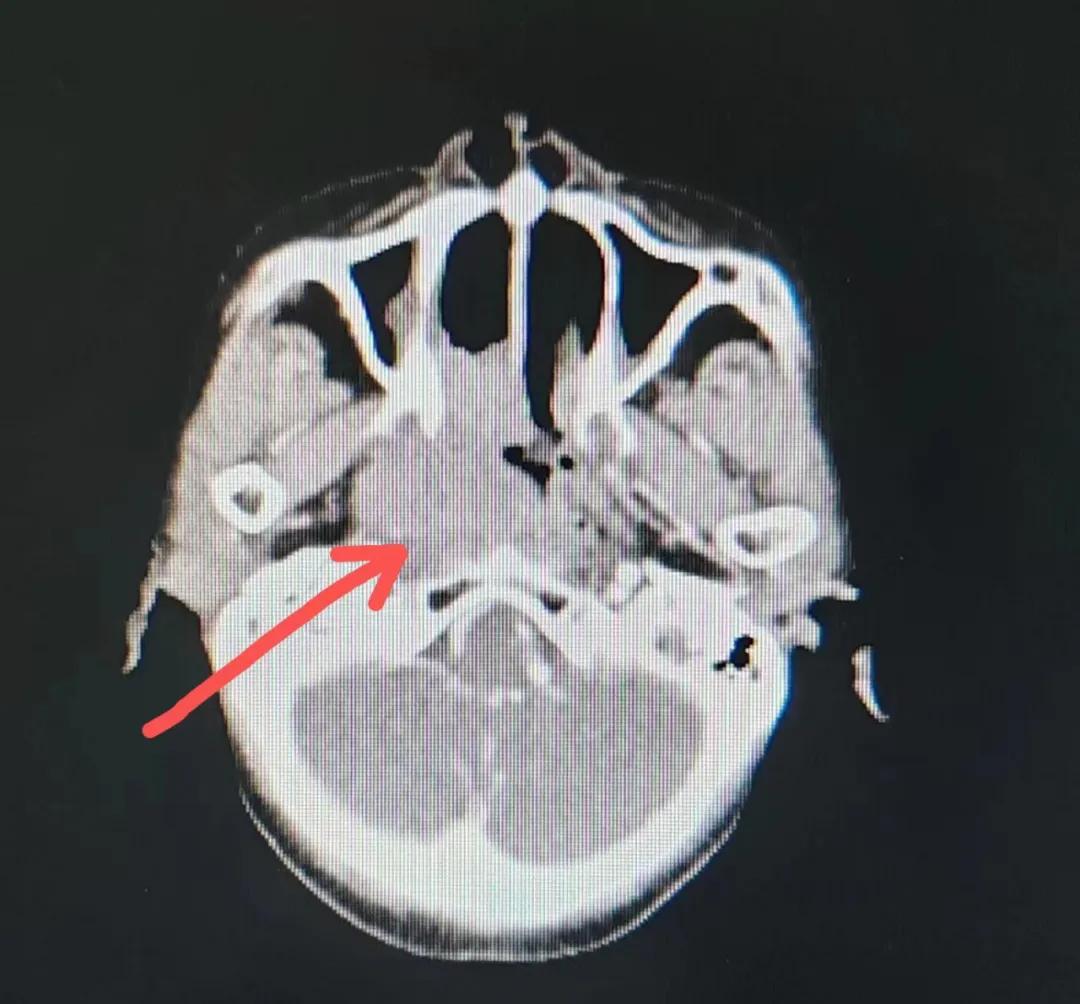

治療前

考慮到患者年齡較大、體質(zhì)差,手術(shù)難度大,且常規(guī)的放射治療難以保護(hù)患者晶體造成患者雙眼視力損傷,放療團(tuán)隊(duì)以最快的速度制定了精準(zhǔn)放射治療方案并開(kāi)始為其實(shí)施治療。僅僅數(shù)日后,老人腫塊出血即得到控制,腫塊明顯縮小,放療20次后腫塊迅速縮?。?/div>